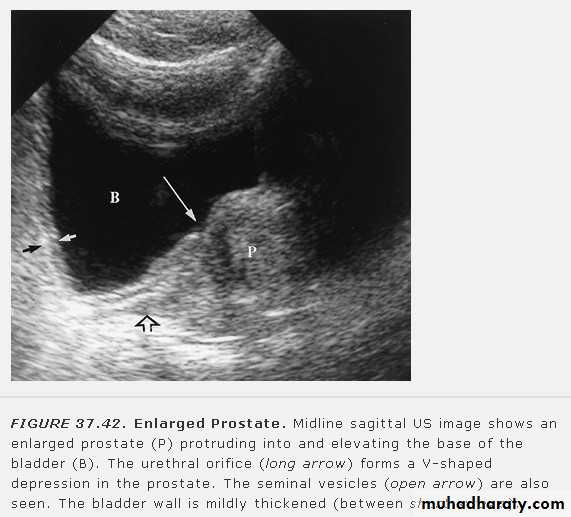

Extra peritoneal rupture• Prostatic enlargement

• Prostatic enlargement is very common in elderly men. It is usually due to benign prostatic hypertrophy but may be due to carcinoma.• TRUS: can show the overall size of the prostate and can diagnose relatively small masses within its substance. TRUS-guided biopsy is used for the diagnosis of prostatic carcinoma

• Trans-abdominal US: used for assessment the size and volume of prostate(the normal prostatic volume is < 20 ml) , measurment of post voiding residual urine volume and determine if there is associated development of hydronephrosis.

• IVU: enlarged prostate may cause round central filling defect at the bladder base and hooking of the distal ureters due to elevation of the bladder base.